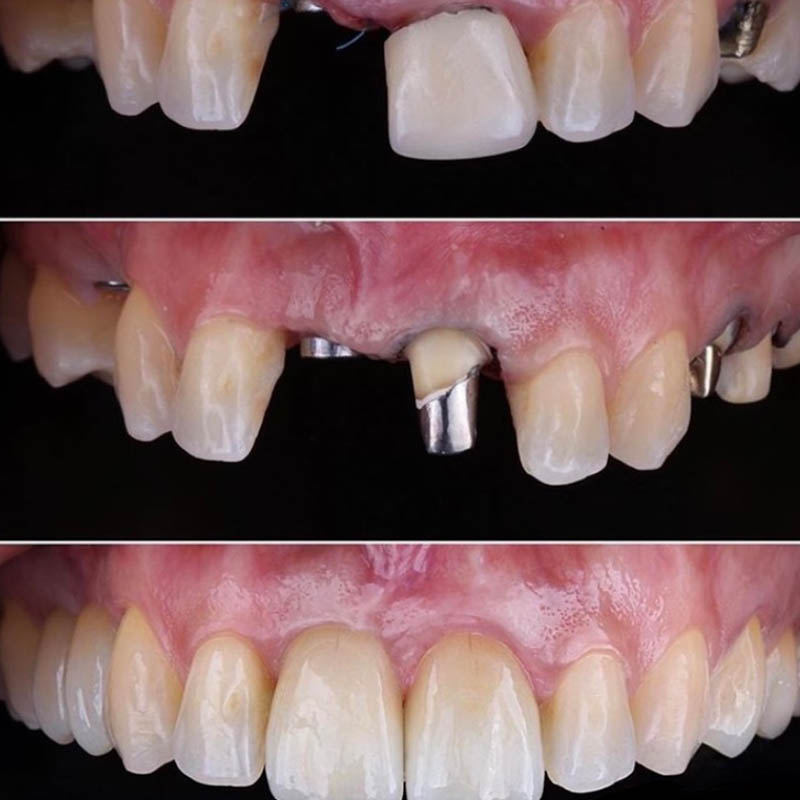

На современном этапе достичь нужного результата стоматологического лечения нередко удается только путем дентальной имплантации. Специалисты клиники Совершенная улыбка тоже активно используют данную методику. При этом в своей деятельности они располагают всеми предпосылками для проведения как быстрой имплантации, когда все действия врач завершает в течение одного посещения, так и операции по классической методике, которой предшествует целый ряд подготовительных процедур, костная пластика.

Успех имплантации в клинике обеспечивается не только мастерством специалистов, высоким уровнем диагностических мероприятий, но использованием качественных материалов, отлично зарекомендовавших себя в сложных клинических случаях или при недостаточной плотности костной ткани. В совокупности такие предпосылки позволяют сократить противопоказания к проведению операции, получить отличные отдаленные результаты. При этом, стремясь обеспечить каждого пациента самым эффективным результатом ортопедического лечения, что гарантирует имплантация, наши специалисты имеют возможность проводить ее моделями разных ценовых категорий. Столь привлекательные финансовые условия позволяют воспользоваться данной методикой людям с любым уровнем доходов.

Примеры работ